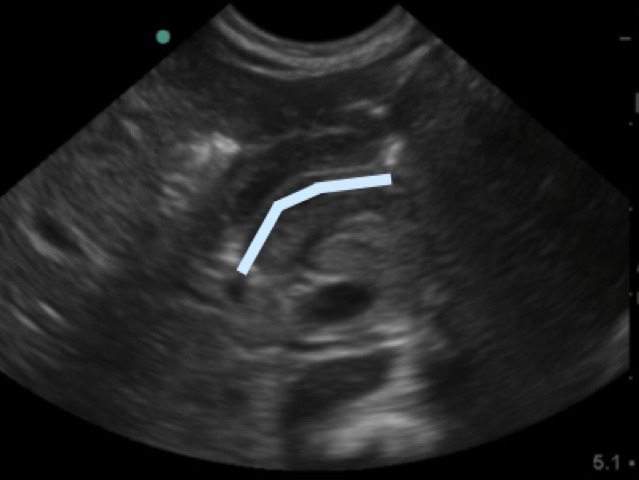

- In between the pyloric muscles is the hyperechoic pyloric channel made up of gastric mucosa.

- Figure 4b.Highlighted pyloric channel made up of gastric mucosa